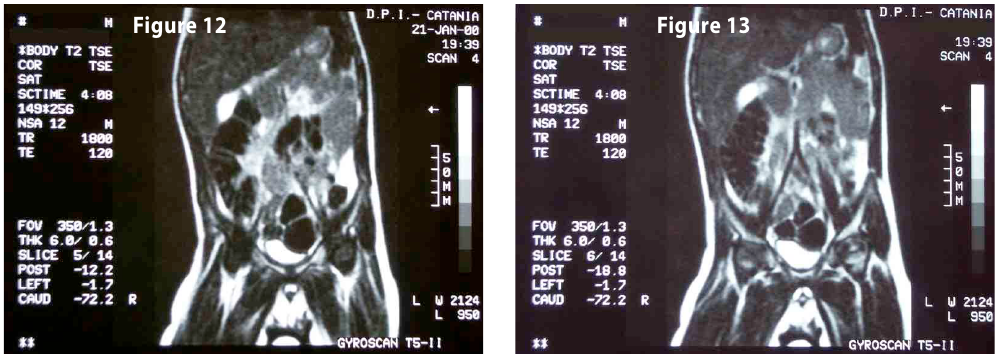

Complete objective response of neuroblastoma to biological treatment.

Figure10-11